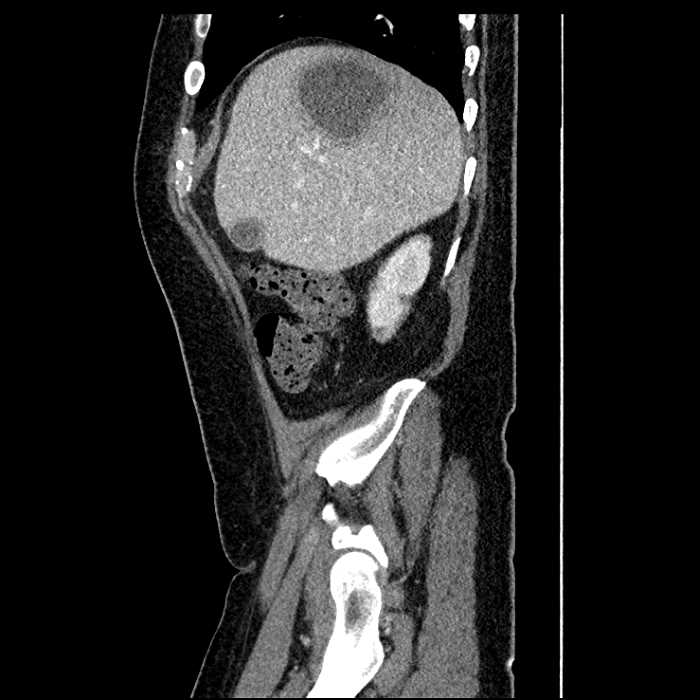

Age: 63

Sex: Male

Indication: Abdominal pain

• Large fluid density structure in hepatic segments 7 and 8 measuring 10 x 7 x 7 cm with internal septation and circumferential ill-defined low density compatible with edema

• Peripherally enhancing subcapsular collections along the anterior margin of the left hepatic lobe measuring 3 x 1 cm and 2 x 1 cm

• Clearly marginated fluid density structure in segment 7 and several other scattered tiny hypodensities, which likely represent cysts

• Hepatic abscess

Acute sigmoid diverticulitis complicated by a small contained perforation and a large abscess in the right hepatic lobe. Additional small subcapsular abscesses along the anterior margin of the left hepatic lobe.

• The classic CT imaging appearance is a double target sign with internal low density surrounded by an internal enhancing rim (capsule) and a low density external rim (edema)

• Abscesses may be unilocular or multilocular

• Gas is present in a minority of cases

Hepatic abscess showing the double target sign with low density internally surrounded by a thin inner enhancing rim (red arrow) and ill-defined outer low density rim (yellow arrow). Blue arrow indicates an internal septation. Red arrows: additional smaller subcapsular abscesses. Red arrow: focal contained perforation associated with diverticulitis.